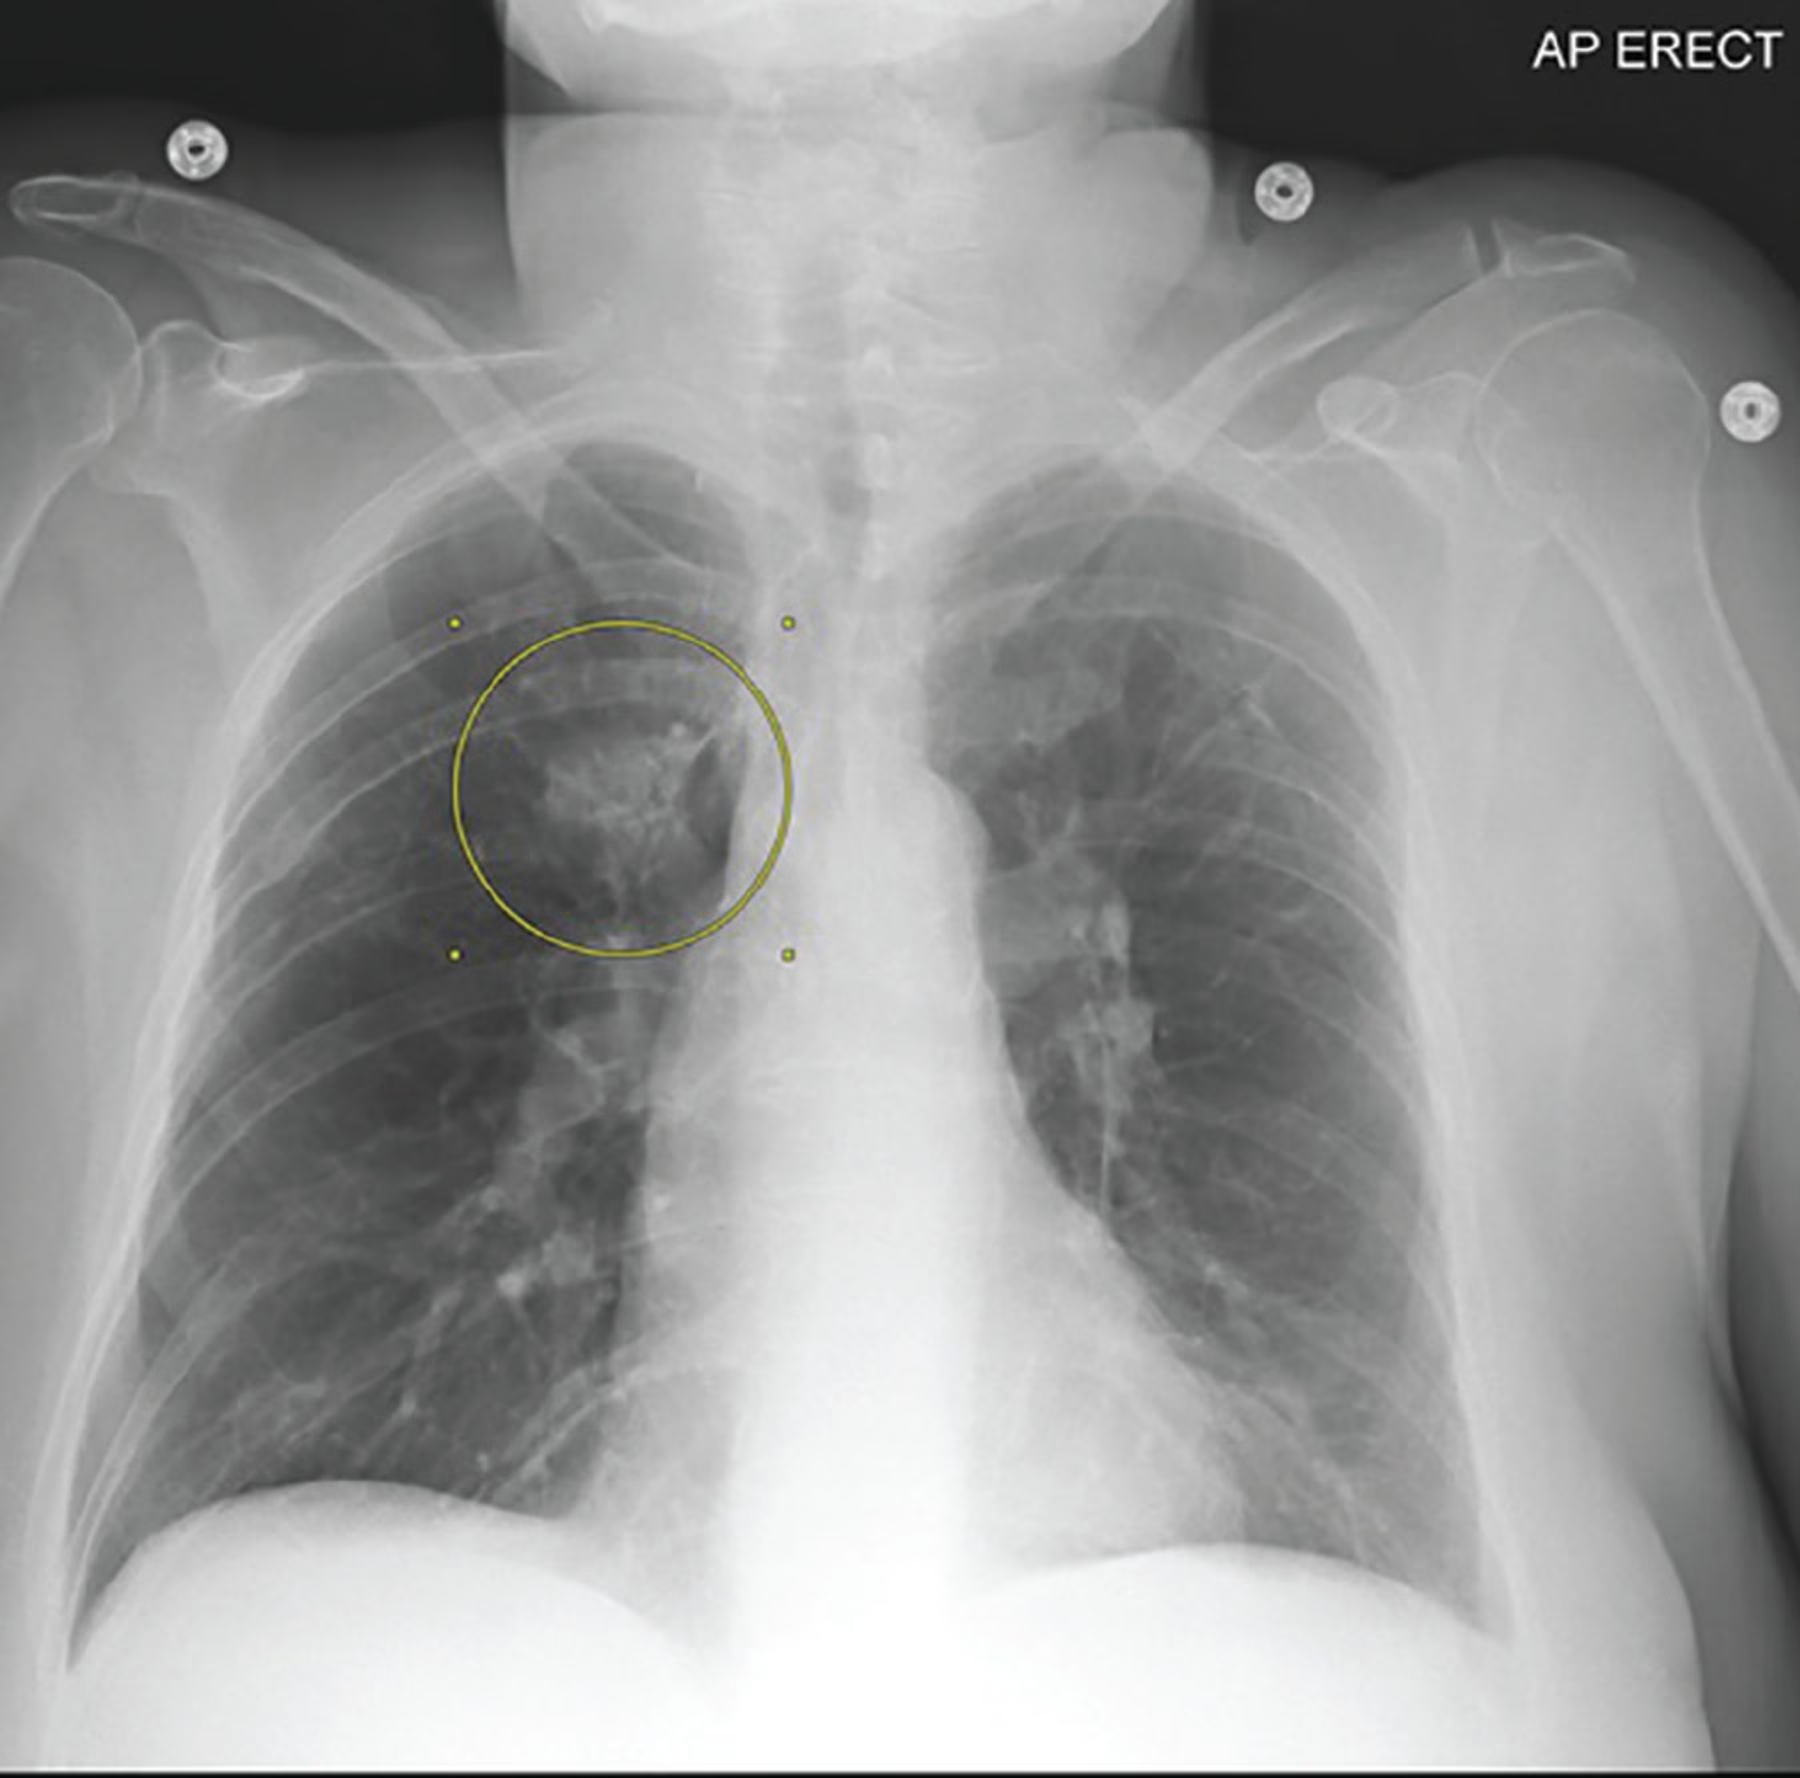

Et røntgenbillede giver lægen et vindue ind til din brystkasse. På et billede af sunde lunger vil lungefelterne fremstå mørke, næsten sorte, hvilket indikerer, at de er fyldt med luft. Hjerteskyggen vil have en normal størrelse og form, og mellemgulvet vil have en glat, buet kontur. Knoglerne, som ribbenene, vil fremstå hvide og skarpe.

Hvis der er abnormiteter, kan de vise sig som:

- Hvide eller tågede områder: Disse pletter eller skygger, kendt som infiltrater, kan indikere tilstedeværelsen af væske, betændelse eller arvæv. Dette er et klassisk tegn på infektioner som lungebetændelse.

- Masser eller knuder: En unormal vækst, som en tumor (enten godartet eller ondartet), kan ses som en velafgrænset plet.

Ved lungebetændelse vil et røntgenbillede ofte vise tætte, hvide eller tågede områder i en eller begge lunger. Disse områder repræsenterer pus og væske, der har fyldt de små luftsække (alveoler) som følge af en infektion.

Lungekræft

Selvom det er en sjælden årsag til hoste, især hos ikke-rygere, kan et røntgenbillede opdage en mistænkelig masse eller knude i lungen. Det er vigtigt at huske, at de fleste hoster ikke er forårsaget af lungekræft, men det er en af de alvorlige tilstande, som lægen ønsker at udelukke.